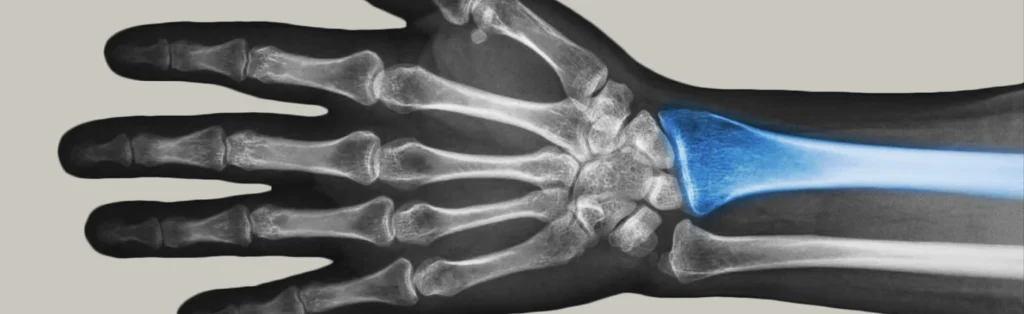

What are distal radius fractures? The radius is the major bone in the forearm that makes up part of the wrist. A fracture or break in the distal...